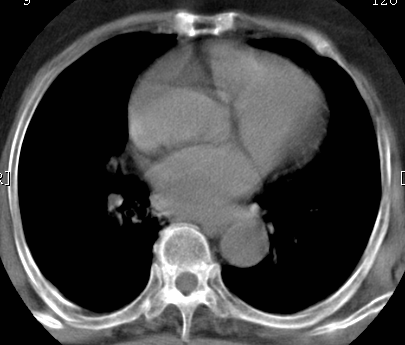

标题: CT26680:肺部右下肺静脉干结节的界定 [打印本页]

标题: CT26680:肺部右下肺静脉干结节的界定

增强适应症

考虑1、周围型肺癌,2肺静脉畸形,前者可能大,建议增强检查。